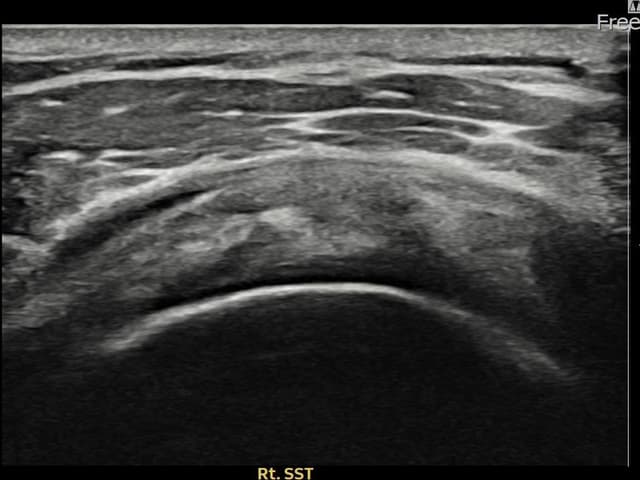

右侧 견갑하근건 关节面侧部分撕裂

7mm × 3mm (肌腱厚度约28%缺损)